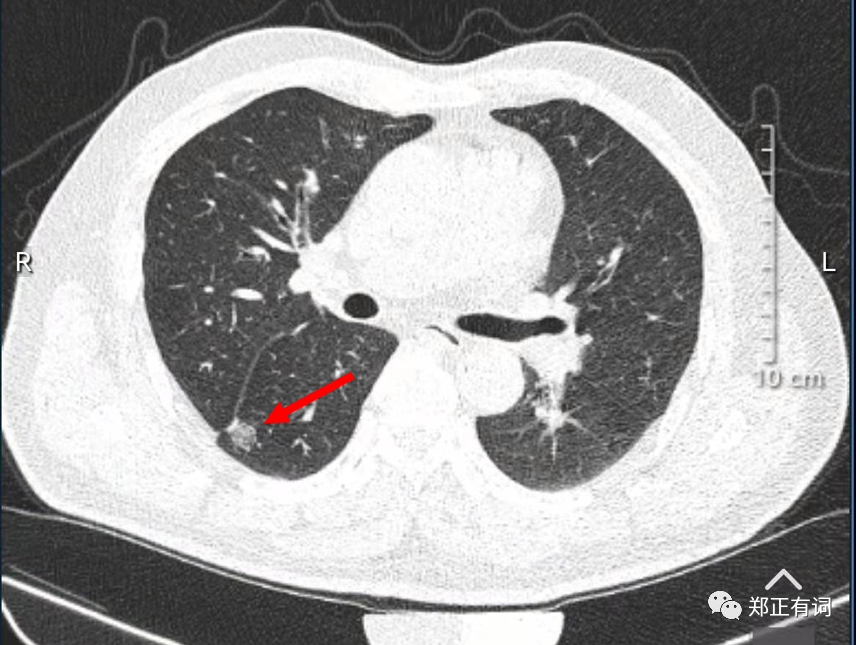

针对40岁以上或抽烟指数达20年包(就是抽烟年数?每天抽烟包数≥20)的高危人群,应该进行积极的低剂量螺旋CT筛查,至少每2年1次。